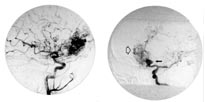

I juni 1999 fikk hun så igjen akutt hodepine, kvalme og oppkast, og det ble påvist blodig spinalvæske. CT caput viste blødning langs høyre side av pons (fig 3) og i fjerde ventrikkel. CT-angiografi viste en malformasjon som tidligere. Hun ble tilrådet konservativ behandling.